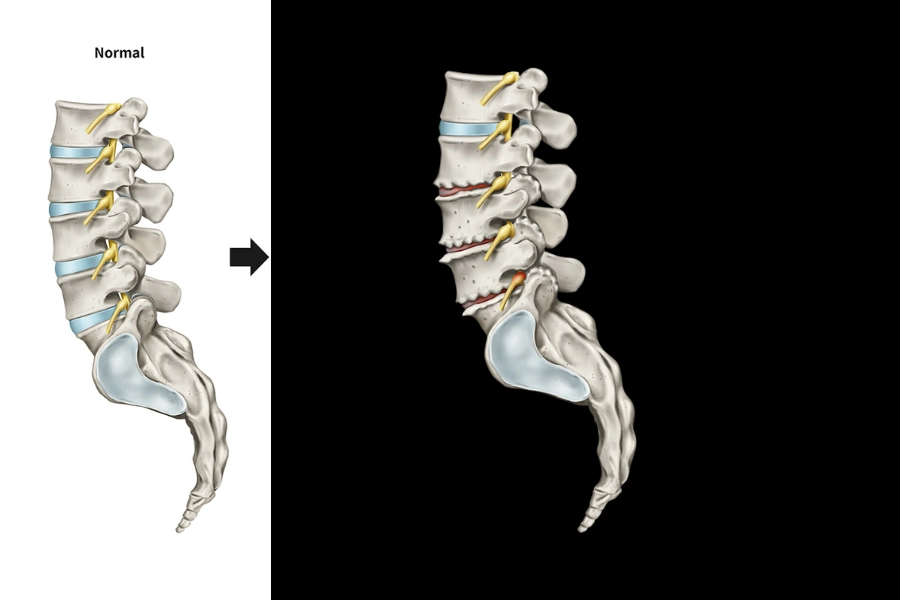

Спондильоз — це результат дегенеративних змін хребта, що проявляються у формуванні остеофітів, тобто кісткових виростів уздовж країв тіл хребців. Такі кісткові розростання виникають як компенсаторна реакція організму на хронічну нестабільність сегментів хребта або тривале перевантаження. У відповідь на поступове зношення міжхребцевих дисків і суглобових поверхонь тіло хребця намагається збільшити площу опори — так і формуються остеофіти, які можуть спричиняти біль, стискання нервових корінців та зниження рухливості.

Спондильоз формується поступово, роками, і є наслідком комплексного впливу різних чинників. Однією з головних причин появи патології є природне старіння тканин. З віком міжхребцеві диски втрачають еластичність і висоту, що призводить до підвищеного навантаження на тіла хребців. Організм відповідає на це формуванням кісткових виростів, які мають стабілізувати хребетний сегмент. Однак така стабілізація часто стає патологічною, обмежуючи рухливість та провокуючи біль.